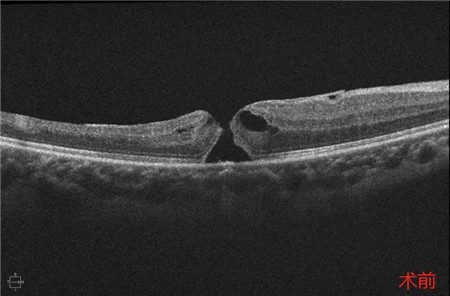

经过详细的眼底检查后,患者被诊断为IRVAN综合征引起的右眼黄斑裂孔,张风院长带领医生团队为患者施局右眼玻璃体切除+剥膜+眼内光凝+气液交换手术,经过半个月的恢复,患者右眼术后视力由术前0.3-达到0.6-的状态,且裂孔呈逐渐闭合状态。